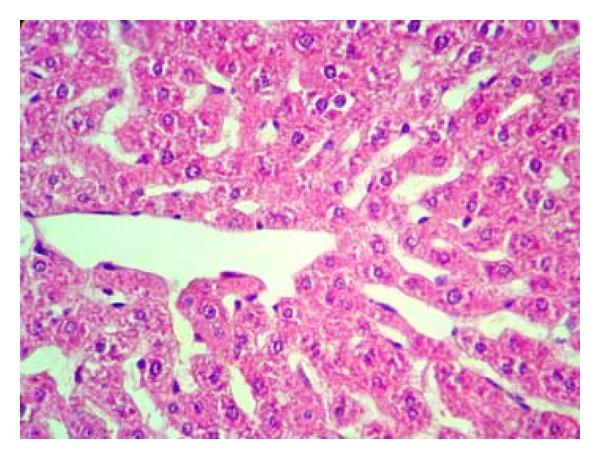

Protective Effects of Green Tea Extract against Hepatic Tissue Injury in Streptozotocin-Induced Diabetic Rats.

Hepatotoxic activity of toluene inhalation and protective role of melatonin.

Liver Dysfunction and Oxidative Stress in Streptozotocin-Induced Diabetic Rats: Protective Role of Turanica.

Quercetin prevents rats from type 1 diabetic liver damage by inhibiting TGF-ꞵ/apelin gene expression.

Ameliorated effects of green tea extract on lead induced liver toxicity in rats.